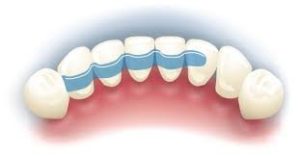

Szynowanie zębów – usztywnienie chwiejących się zębów szyną z włókna szklanego.

szynowanie

Szyna na zębach.